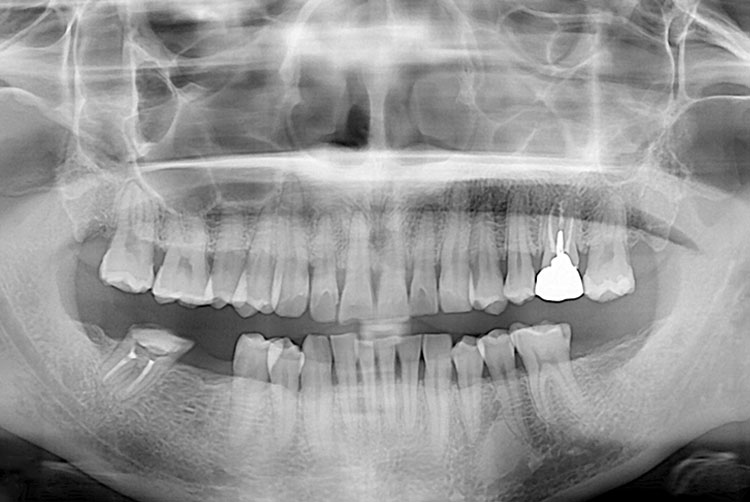

[임플란트] 임플란트

치료전 : 2018-11-12